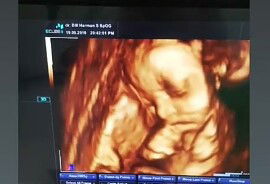

Bun.. aku hamil udah 32week.. tpi bb janin ku baru 1300gr normal nya 1900gr bun. Aku udah menjalani 5 kali usg karna pengen ngontrol bb janin.. perut ku kecil sekali bun.. sampai2 aku masih bisa tengkurap.. padahal udah jalan 8 bulan.. aku sedih betul bun.. hpl 24 november 2019.. tinggal 1 bulan stengah lgi.. apa masih ada harapan baby ku bisa di atas rata2 bb nya.. hasil usg sih sempurna cuma kecil bun baby nya? takut nya prematur dia lahir nanti kan kasihan.. apa ada bunda yg mengalami sperti saya.. gimna itu bun ? Apa kah pas sudah di lahirkan dia masih sehat2 sajaa.. ini fto usg trakhir bun pas usia 31week